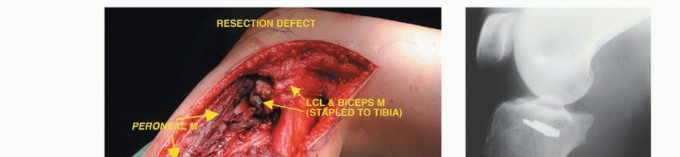

الاستئصال من النوع الأول (Type I Resection):

- الإشارة: يُستخدم لعلاج الأورام الحميدة العدوانية والأورام الغرنية منخفضة الدرجة التي تسببت في تدمير قشري كبير للشظية القريبة.

- الإجراء: يشمل إزالة الشظية القريبة، وغلاف عضلي رقيق من جميع الأبعاد، وموقع ارتباط الرباط الجانبي الوحشي (LCL). يتم الحفاظ على العصب الشظوي المشترك وفروعه الحركية، ويتم استئصال المفصل الظنبوبي الشظوي داخل المفصل.

- الحفاظ: يتم الحفاظ على العصب الشظوي والشريان الظنبوبي الأمامي عادةً.

الاستئصال من النوع الثاني (Type II Resection):

- الإشارة: يُستخدم لعلاج الأورام الغرنية عالية الدرجة، والتي عادةً ما يكون لديها تدمير قشري كبير مع امتداد خارج العظم.

- الإجراء: يشمل إزالة الشظية القريبة والمفصل الظنبوبي الشظوي، والحجرات العضلية الأمامية والجانبية، والعصب الشظوي، والشريان الظنبوبي الأمامي بشكل كامل. يتطلب هذا النوع ربط الشريان الظنبوبي الأمامي وقد يتطلب أيضًا التضحية بالشريان الشظوي.

- الحفاظ: لا يتم الحفاظ على العصب الشظوي والشريان الظنبوبي الأمامي.